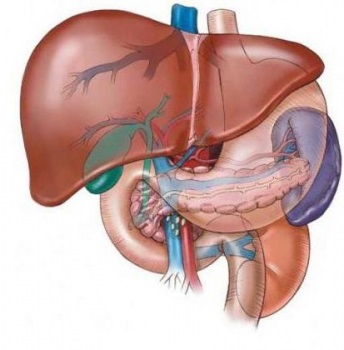

Hepatobiliaris rendszer áll az epehólyag, a máj és epeutak. Fő feladata a kialakulását és a közlekedés az epe, amely a máj által termelt sejtek. Ez mozgatja a csatornákon keresztül az epehólyagban, ami további tározó. Az epe, hogy van benne tárolt, több koncentrálódik a májban 5-10-szer. Az étkezés után megkapja a patkóbél felé. Anatómiája epe rendszer más, mint a máj és az epehólyag magában májon belüli epevezeték, amelyek közvetlenül a májban. Ezek kezdődnek epe hajszálerek, fokozatosan halad a nagyobb epeutak, amelyek messze túlmutatnak a májat. Extrahepatikusan epeutak és a máj bemutatott közös megosztott csatornák, amelyek együttesen alkotják a közös epevezeték.

Anatómiája epe rendszer kezeli a máj központi szerve az epe képződését, hanem a legfontosabb szerve a férfi. Itt van, hogy a kialakulását a legtöbb a test energia, mert 20% -a sejtek tömege teszik ki a májat, hogy a mitokondriumok ATP szintéziséhez. A máj a legnagyobb mirigy az emberi szervezetben, ami egy állandó belső környezet. Ő központi szerepet játszik a fehérje, zsír és szén anyagcserét és a gyógyszerek metabolizmusát. Máj tartozik azon kevesek egyike, hogy a szervek folyamatosan ki vannak téve a nehéz terhek, de ugyanakkor képesek visszaállítani a saját rövid időn belül. A test, a következő funkciókat: